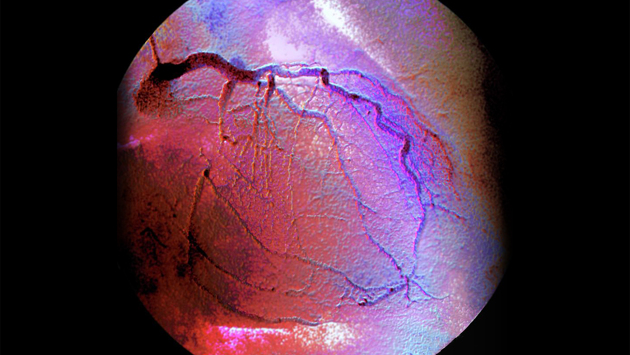

При создании модели ученые использовали реальные результаты исследования инвазивной коронарной ангиографии пациентов с ишемической болезнью сердца. Таким образом, им удалось смоделировать поток крови в условиях, максимально приближенных к реальной диагностике. На основе этих данных исследователи создали геометрическую модель участка артерии со стенозом. Используя данные о пульсации давления на входе в исследуемый участок артерии, они провели гемодинамическое моделирование и получили информацию о течении крови для полного кардиоцикла.

Результаты показали, что за стенозом формируется низкоскоростной вихревой поток, а также возникает область, где вязкость крови увеличивается до двух раз. Кроме того, из-за влияния стенок артерий поток становится значительно асимметричным. Это позволяет предположить, что альтернативы трехмерному моделированию для исследования сложных участков реальных сосудов нет. Моделирование артерии после предполагаемой реваскуляризации показывает отсутствие вихря и существенно более равномерные потоки в рассматриваемой области, скорость потока при этом замедляется до 30%. Следующая цель ученых — запуск в кровоток наночастицы магнетита, которые позволят «визуализировать» процессы в сосудах. Этот недорогой материал не вызывает воспалений и в выводится естественным путем. Технологии изготовления наночастиц хорошо отработаны.Ме